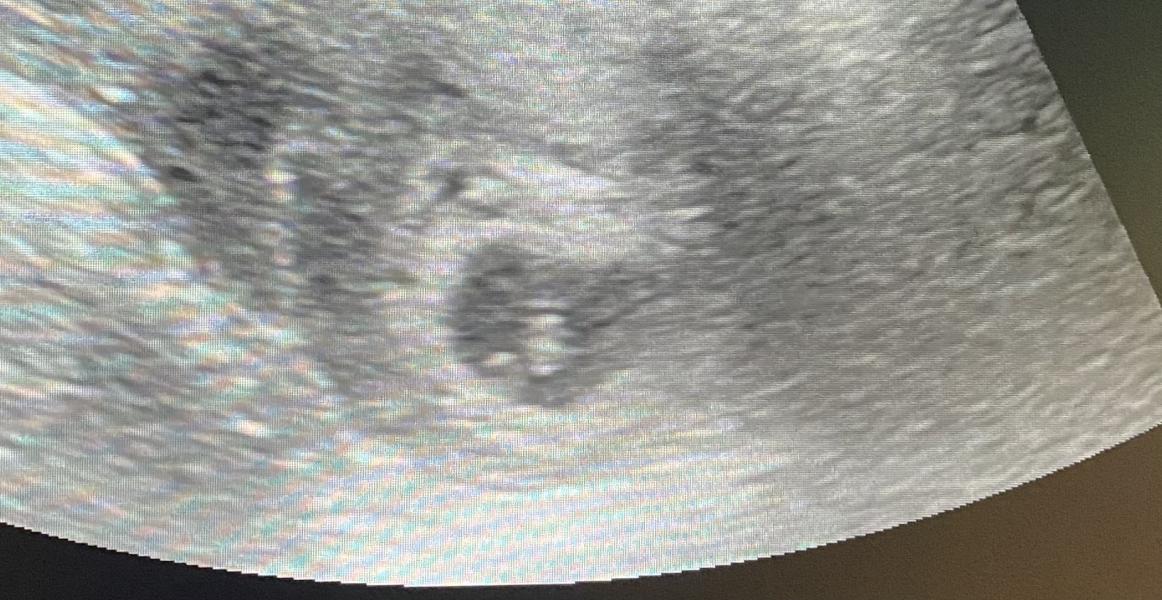

Первое УЗИ при беременности: 5-6 недель, сердцебиение

вот наша радость🥰 сердцебиение есть🙏🏼 по узи 5-6нед❤️

Первое узиРанняя беременностьСердцебиение плода